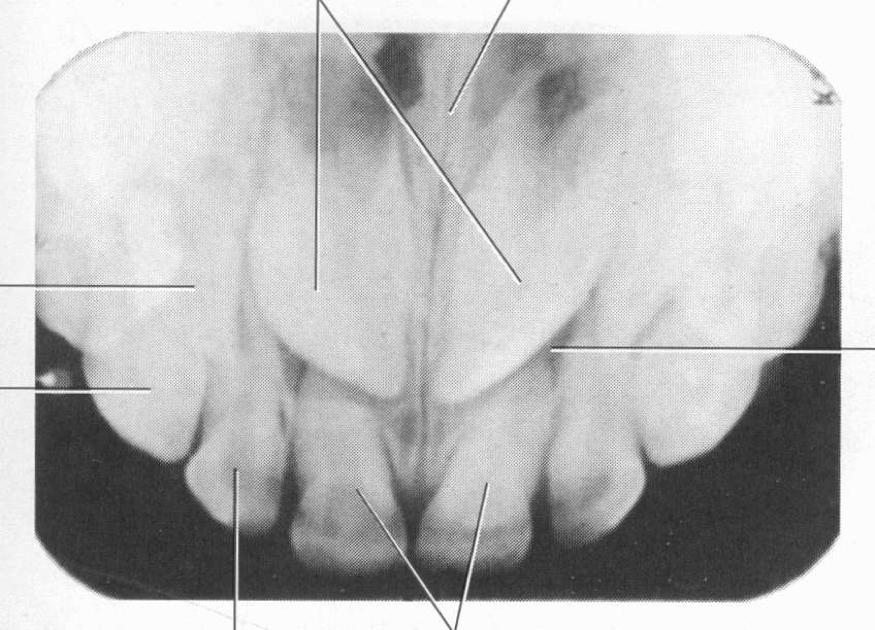

Topographical Radiograph

Produces a large PA radiograph. Topographical occlusals yield a greater amount of information of the alveolar crest and the apical areas than PA’s.